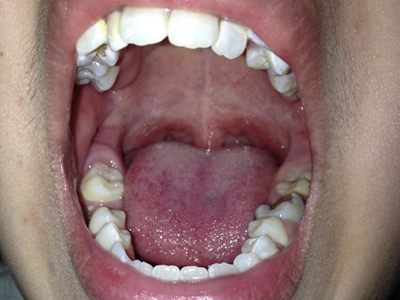

牙龈

红肿

智齿冠周炎第二颗大牙后边又长一颗牙伴牙龈红肿图

智齿冠周炎患者在进行口腔检查时,可见牙槽骨末端有萌出位置及方向异常的牙齿,常不能完全萌出,而是只显露一部分,可伴有周围牙龈组织轻微红肿、疼痛。